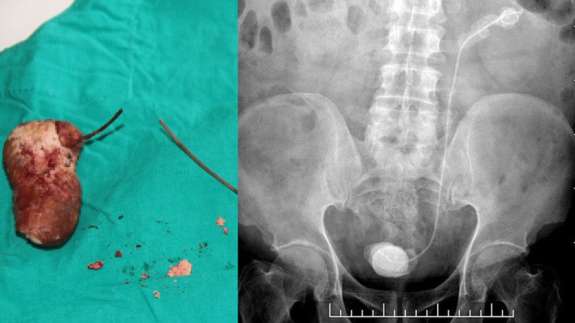

Unutkanlığın böylesi! 7 yıl boyunca içinde kalmış